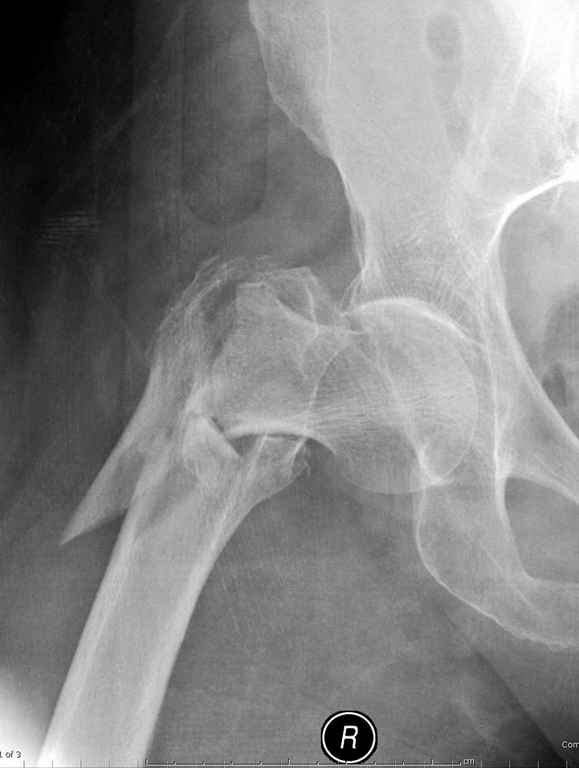

Здесь пара похожих случаев.

Не солидно экономить на пленке, это не делает чести презентации. Такие ограниченные нестандартные снимки приводят к тактическим ошибкам.

Предугадать распространение линий перелома при чрезвертельных и оскольчатых переломах трудно, поэтому для принятия правильного решения рекомендуется Компьютерно Томографические исследование.

При отсутствии КТ, снимок на вытяжении поможет увидеть общую картину расположения отломков, особенно потенциальные места введения импланта. Риск раскола в этом случае огромный, поэтому больной должен быть дообследован.